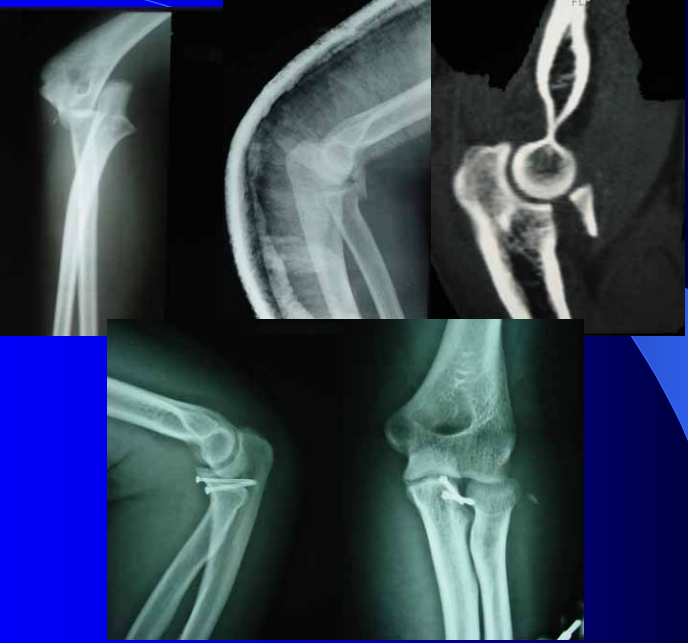

冠突是一个非常重要的稳定结构

• Ⅰ型和Ⅱ型单纯冠状突骨折,发生后方半脱位的风险很小,允许早期活动

• 即使单纯Ⅲ型骨折,在很小的生理应力下也有可能发生后方半脱位,特别是在屈肘60°~105°,支持对Ⅲ型损伤ORIF